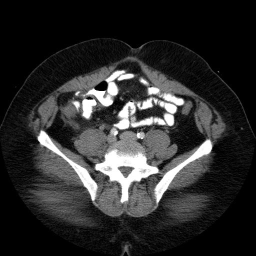

These are images from a contrast enhanced abdominal CT.

Fluid in the right paracolic gutter, and a thickened, inflamed appendix with thickening of the adjacent cecal wall.

Differential: Acute appendicitis is by far the most likely diagnosis.

No appendicolith is seen in this case.

The appendix is normally less than 7 mm in diameter, or if fluid filled, the wall can be up to 3mm thick. This appendix is distended, and the adjacent stranding and fluid indicates the inflammatory process which is causing peritoneal irritation and pain. Here is a series of images showing a normal appendix using similar technique. Note the thin walls of the normal appendix.